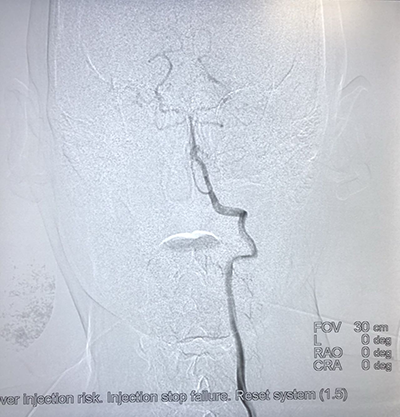

![]() | ![]() |

| (脾功能亢进的介入治疗) | (食道支架植入术) |